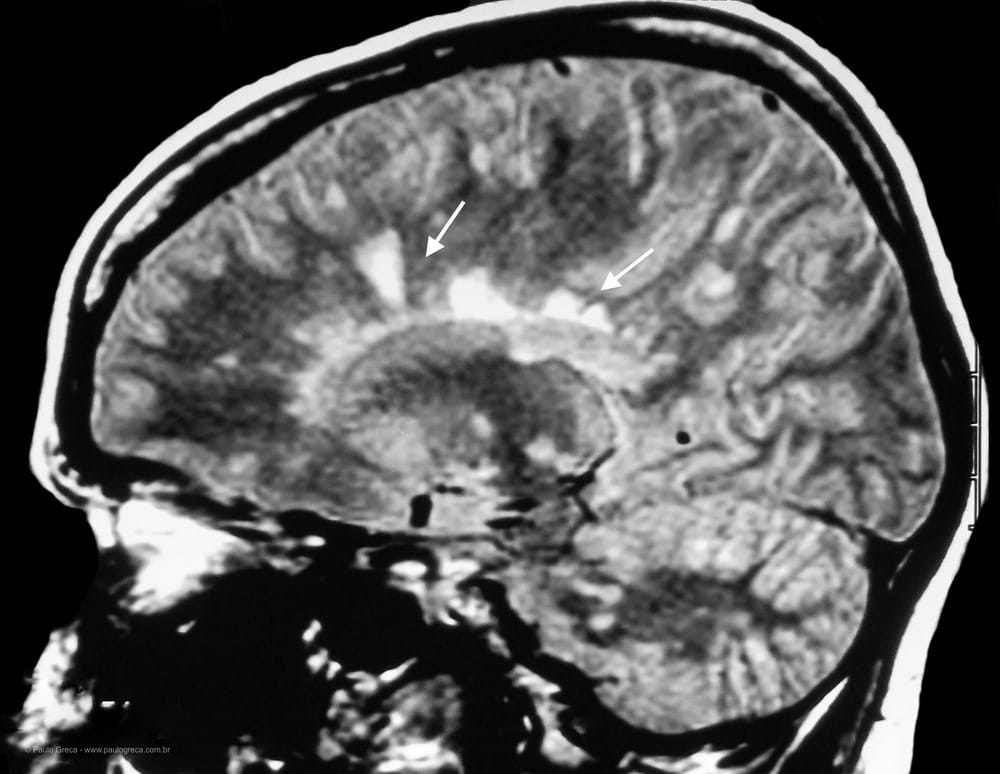

Para que o quadro clínico do paciente seja considerado como enxaqueca, as crises devem ter um conjunto de características já conhecidas e aceitas pelos especialistas. É sabido que na rotina da clínica médica, pessoas com manifestações da migrânea, geralmente apresentam resultado negativo para exames de laboratório, neurológicos e complementares, tais como raio-X, ressonância magnética ou eletroencefalograma. Apesar destes processos investigativos não identificarem a síndrome, servem para que se possa excluir prováveis causas das dores relacionadas a doenças, tais como a hipertensão arterial, sinusite, moléstias infecciosas, câncer, HIV, entre outras.